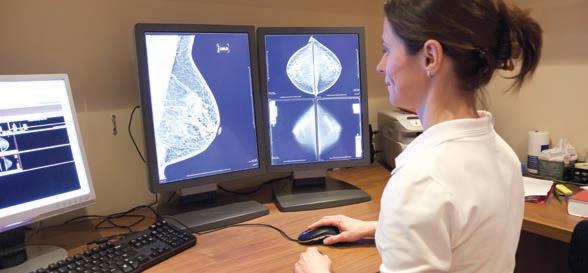

Calls for breast density reporting

All

women having routine mammography should be told if they have dense breasts and are of greater risk of breast cancer, the peak body for radiologists says.

In a position statement published last December, the Royal Australian and New Zealand College of Radiologists joined calls for widespread breast density reporting to inform patients of their particular risk.

Breast density — the ratio of fibro-glandular tissue to fatty tissue — can be an independent risk factor for breast cancer and can also affect the accuracy of mammogram reporting, because dense tissue and tumours both appear white in mammograms.

About 40-50% of women have dense breasts, but currently there is no national policy on optimal management of notifying women of breast density, with only Western Australia and South Australia requiring patients to be assessed and notified.

Last year, the US Food and Drug Administration introduced a requirement that breast density be reported on all mammogram results nationwide, and for that report to go to both clinicians and patients. Previously this was the rule in some states, but not in others.

There are now calls to have a consistent national policy on breast density notification across Australia.

“While a future risk-based model for breast cancer screening is being developed, RANZCR recommends mandating the reporting of breast density in both screening and diagnostic settings,” the college statement said.

Higher risk

One in 10 Australian women are estimated to have Breast Imaging-Reporting and Data System (BI-RADS) category D density, or extremely dense breasts.

“Studies have demonstrated that extreme (mammographic breast density) is associated with a 2.1fold increased risk of breast cancer compared with the average risk scattered category of BI-RADS category B,” the RANZCR said.

Meanwhile a new Australian trial is looking at the potential harms and benefits of notifying women of the risks associated with breast density during routine breast screening.

A randomised control trial undertaken in Queensland aims to examine the longer-term effects of notifying women about breast density in relation to breast cancer risk factors.

The trial, which started last September in BreastScreen Queensland clinics, has been outlined in a study protocol published in the Medical Journal of Australia

The researchers said there had been continued international debate surrounding the pros and cons of widespread breast density notification. They hope the evidence from the study would guide best practice and policy for breast screening in Australia and abroad.

The trial is a world-first in assessing the impact of notification (versus not) using a randomised design, and to also test different ways of telling women that they have dense breasts on mammograms.

It will look at the benefits and harms of notification, including the effect over time – two years or more.

The study will look at psychological outcomes of notifying patients – whether they feel anxious, confused or informed – and also whether it influences them to have follow-up GP consultations and supplemental breast screening.

Researchers hope the findings will help BreastScreen Australia to develop best practice policies for notifying women of breast density and to find the most effective way.

ED: Congratulations to BreastScreen WA, which turns 35 this year after starting as a pilot program in 1989. It targets women aged 50-74 years, offering free screening every two years, but women can access it from the age of 40. Go to www.breastscreen.health.wa.gov.au